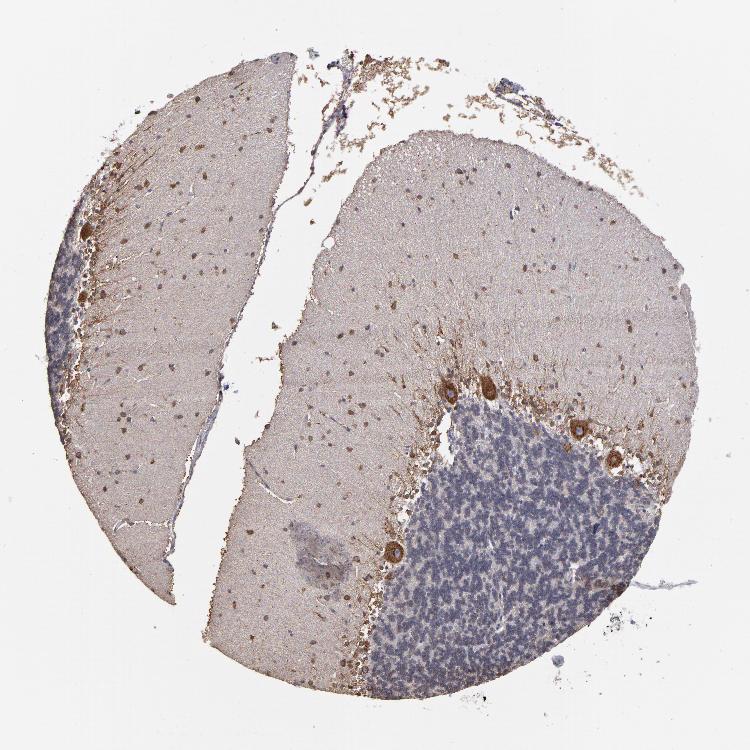

CEREBELLUM - Antibody stainingi

Antibody staining in the annotated cell types in the current human tissue is reported as not detected, low, medium, or high, based on conventional immunohistochemistry profiling in selected tissues. This score is based on the combination of the staining intensity and fraction of stained cells.

Each image is clickable and will lead to virtual microscopy that enables deeper exploration of all samples and also displays staining intensity scores, fraction scores and subcellular localization as well as patient and tissue information for each sample.

Antibody HPA002529Antibody HPA002632Antibody CAB019323

Purkinje cells MediumHighHigh

Cells in granular layer LowLowLow

Cells in molecular layer HighMediumMedium